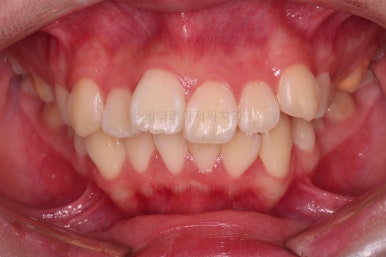

초진 시, 입 안의 모습입니다.

치아가 많이 삐뚤어요.

공간이 부족해서 앞니가 앞으로 많이 뻐드러졌고, 삐뚤한 양상 때문에 덧니가 되었네요.

어금니 맞물림도 좋지 못한 앵글씨 2급 부정교합 상태였어요.